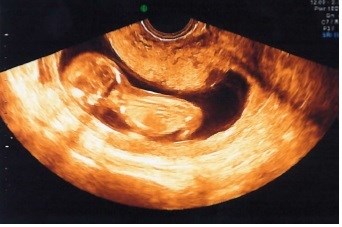

Baby-bølle ville ikke ligge i profil, men valgte at ligge med røven/ryggen til, og ville ikke rigtigt vende sig - på et tidspunkt svømmede den rundt og det så ud som om den ville være samarbejdsvillig, og der blev hurtigt taget et par billeder, som de vurderede nakkefolden ud fra. 1:7198, er da ret godt (jeg er 33 år) Hele seancen tog en god halv time, indtil vi måtte konstatere, at vi nok ikke fik bedre billeder en dem jeg har vedhæftet.

Det ene billede er hurtigt taget, mens bøllen lå på siden, det andet mens bøllen lå med røven/ryggen til